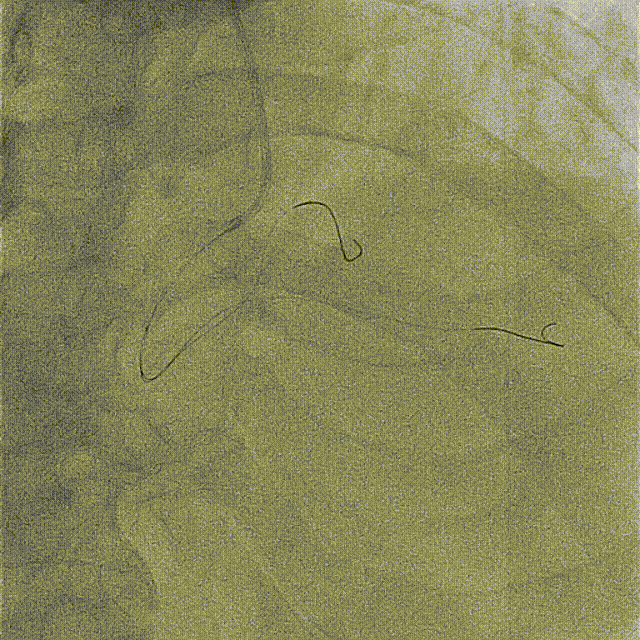

导丝顺利通过闭塞段,但未见前向血流。

使用2.5*15mm球囊以6-8ATM压力预扩张。

预扩后右冠远端显影,远段及PD开口处可见血栓,抽吸出约2cm长血栓1条。

抽吸一次后PD血流好转,仍见血栓影,PL未见显影,再次抽吸。

于PD抽吸后血流消失,PL显影,送导丝到PL远端。

反复尝试PL、PD抽吸及球囊扩张。

先后于3条分支球囊低压扩张,及冠脉内注入欣维宁。